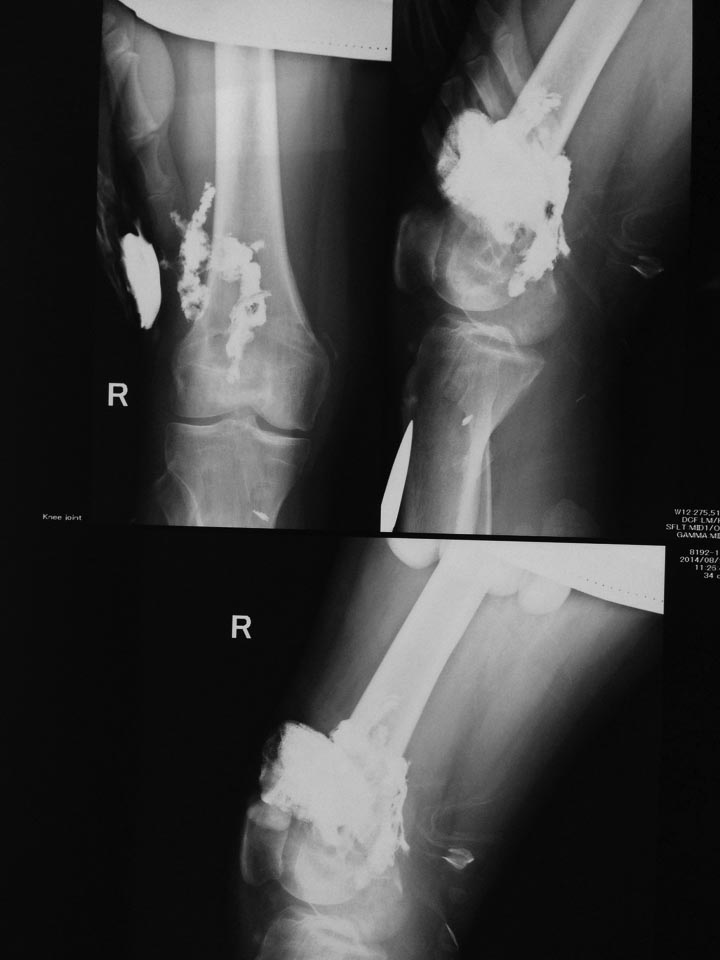

В понедельник сделали фистулографию и получили вот такую картину.

В экстренном порядке взяли на ревизию, и тут все началось - гнойные

затеки по всему бедру, по всем костно-мышечным каналам бедра до в/3,

книзу доходит до заднего отдела сустава.